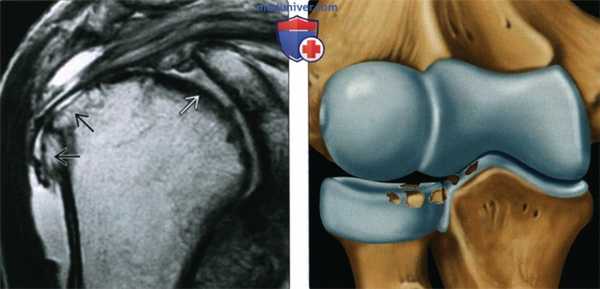

(Слева) МРТ, корональная проекция, режим протонной плотности: признаки ОА, включая полную утрату хряща, субкортикальный склероз и верхние краевые остеофиты. Определяется истончение сухожилия надостной мышцы. На других срезах визуализировались признаки полнослойного разрыва вращательной манжеты. Выпот визуализируется как в плечевом суставе, так и в подакромиально-поддельтовидной сумке.

(Справа) Рисунок: признаки ОА локтевого сустава, включая несколько фокальных дефектов хряща. ОА часто является результатом предшествовавшей травмы и/или наличия свободных тел.